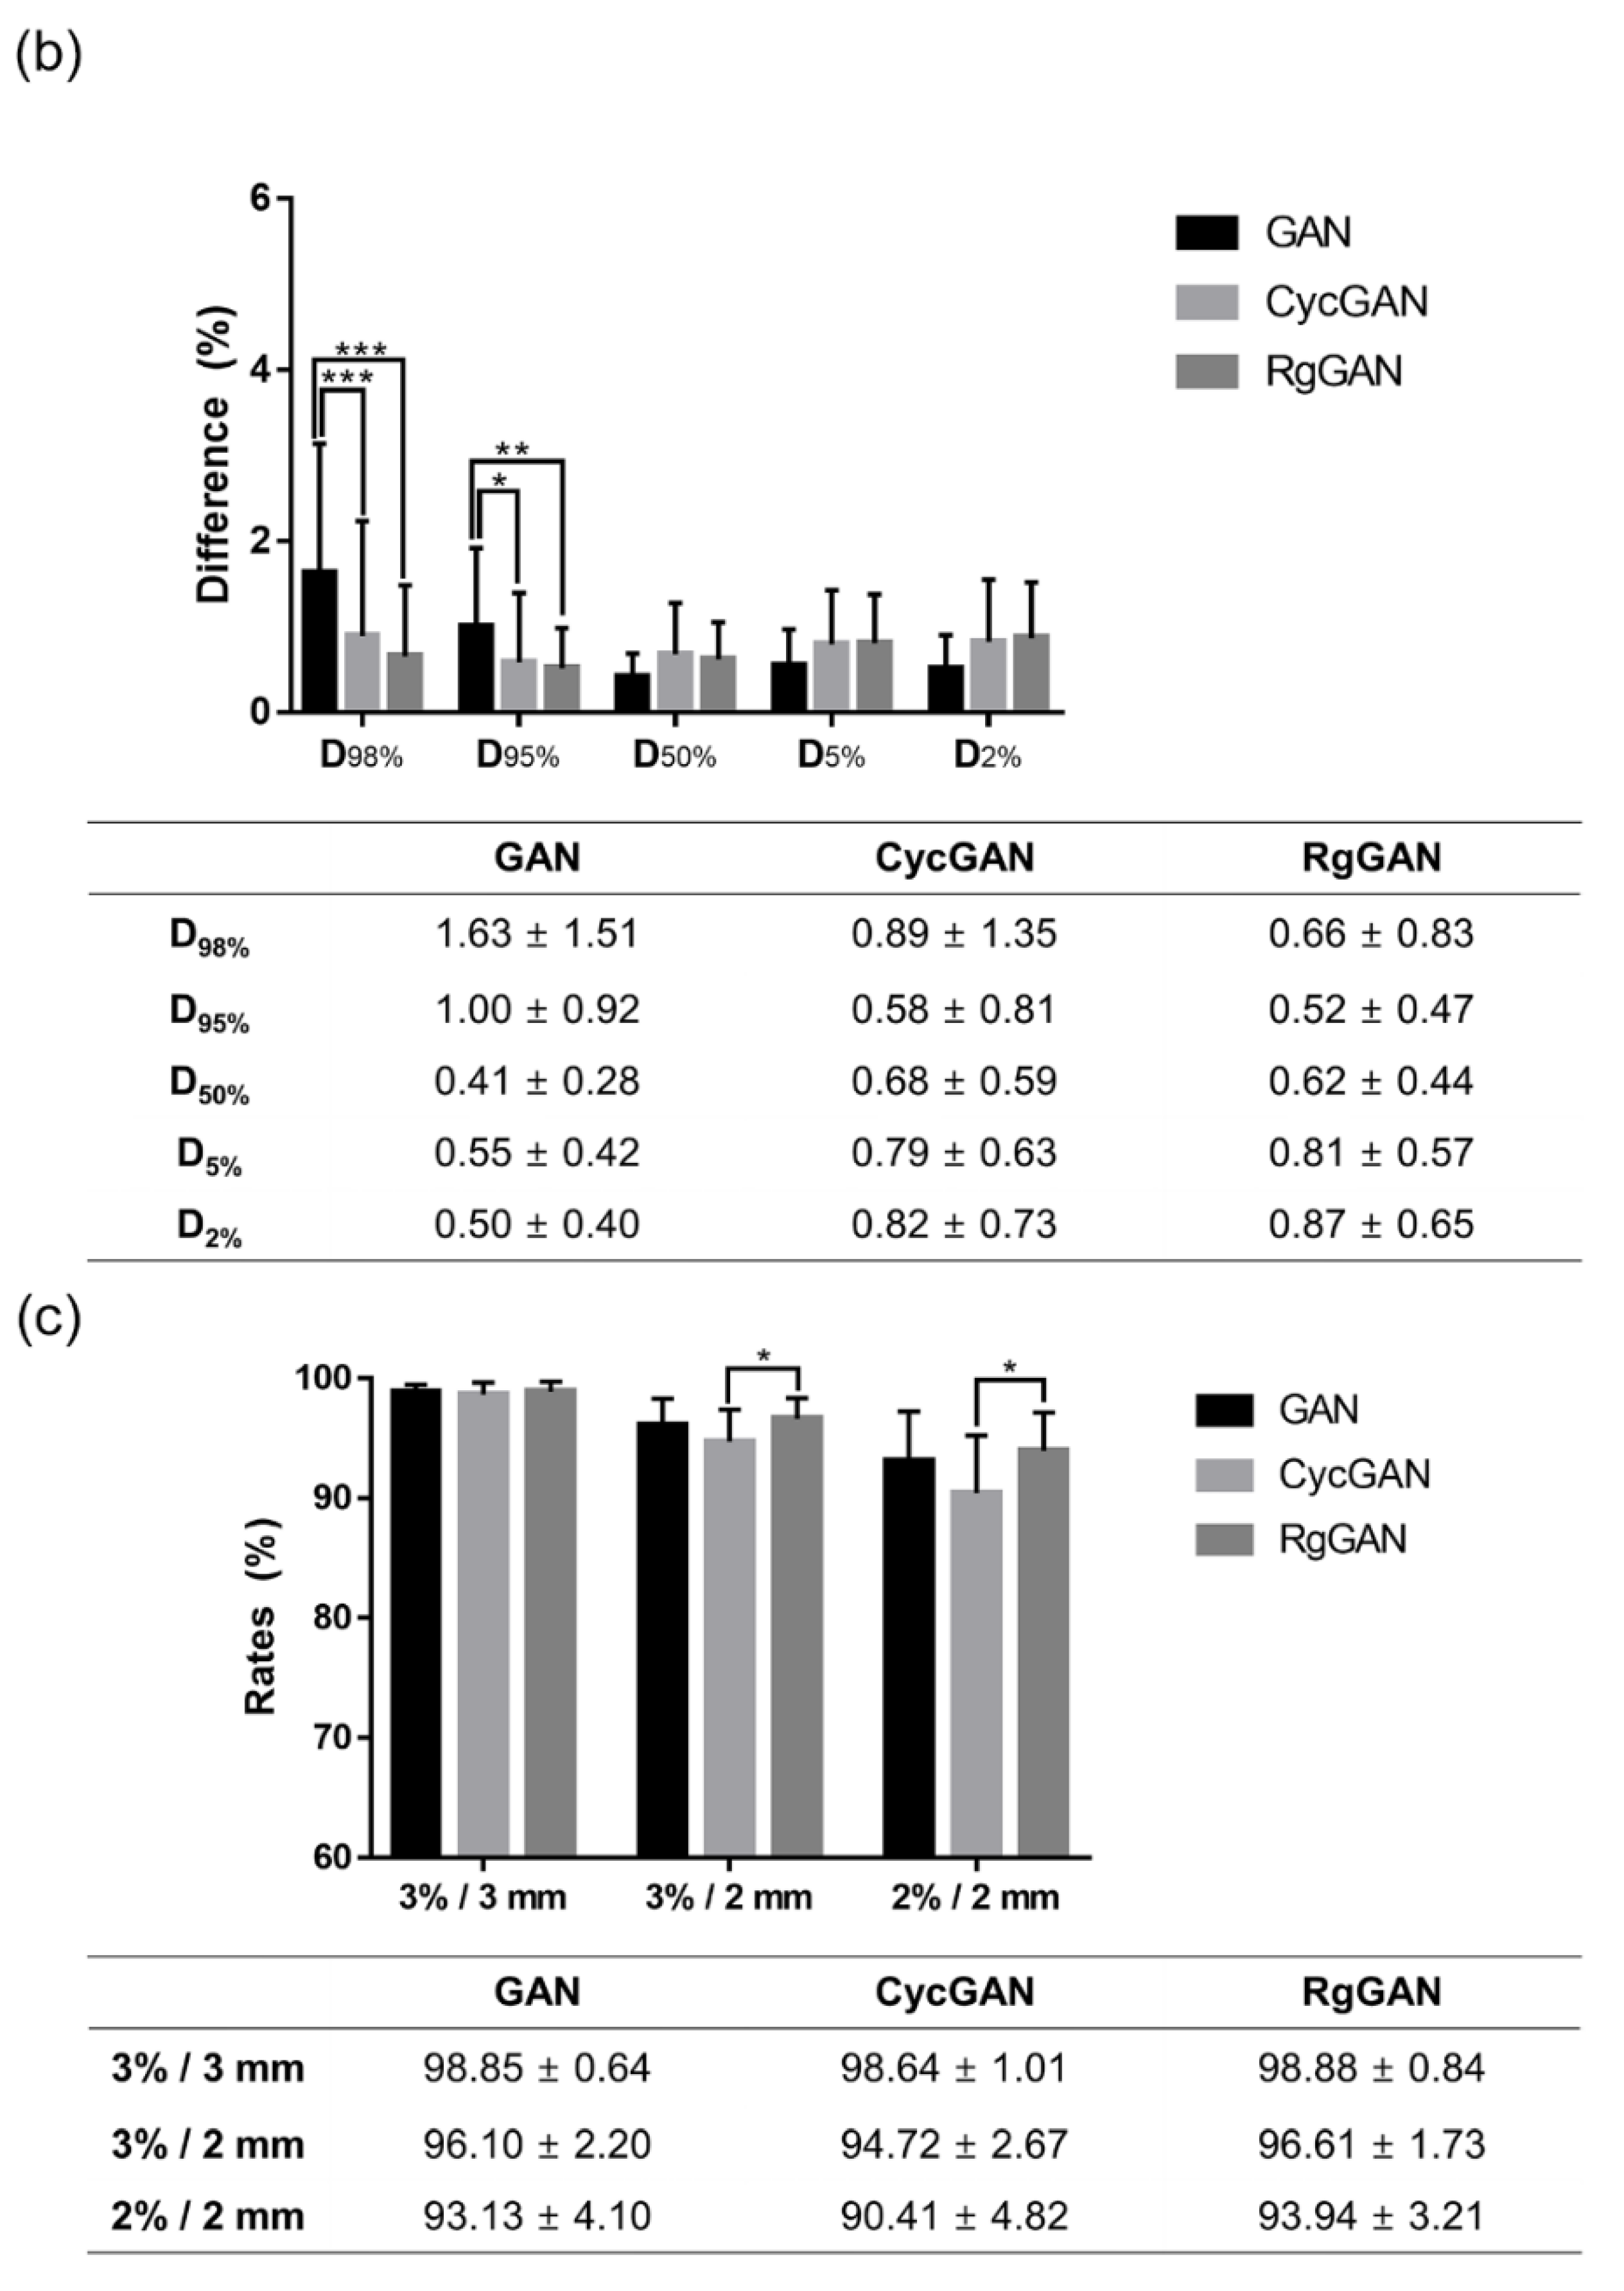

3.3. Dosimetric Comparison